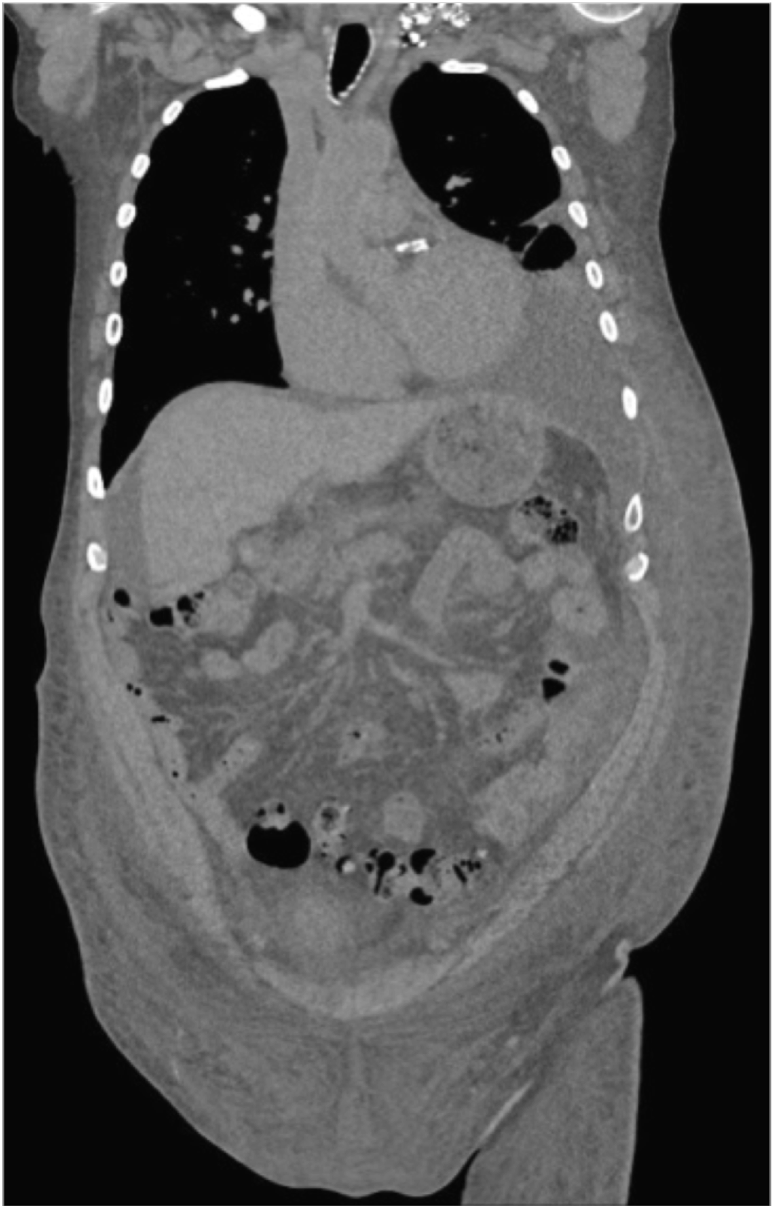

Case Presentation: A 70-year-old man presented with 5 months of anasarca and recurrent chylous ascites and left chylothorax. He had symptoms of dyspnea, orthostatic hypotension, bloating, early satiety, 20-pound unintentional weight loss, anasarca, and left periorbital purpura. He was a 25 pack-year current smoker with a past medical history including type 2 diabetes mellitus, hypothyroidism, and coronary artery disease status-post coronary artery bypass graft 2 years prior. Physical exam revealed left periorbital purpura, decreased breath sounds in left lower lobe, protuberant abdomen without tenderness, thickening of abdominal wall and skin of extremities with 3+ pitting edema to pelvis, with normal cardiac exam and no appreciable lymphadenopathy. Significant labs included hemoglobin 12.7, serum albumin 2.3, alkaline phosphatase 271, NT-proBNP 23,354 pg/mL, and high sensitivity troponin 189 ng/L. The total ascitic protein was 2.5, ascites albumin 1.0, with a serum-ascites albumin gradient (SAAG) of 1.3 The elevated SAAG and total ascetic protein of 2.5 suggested a cardiovascular etiology. Subsequent transthoracic echocardiogram revealed increased LV and RV wall thickness, biventricular systolic dysfunction, and strain pattern consistent with amyloidosis. Fat pad biopsy found a peptide profile consistent with AL (kappa)-type amyloid deposition, and liver biopsy showed amyloid deposition in portal tracts and vessel walls consistent with hepatic amyloidosis, but not meeting criteria for cirrhosis.

The patient was ultimately diagnosed with AL (kappa light chain) cardiac and hepatic amyloidosis. He was prescribed furosemide, spironolactone, midodrine, and cyclophosphamide-bortezomib-dexamethasone therapy, with a recommendation to follow a medium chain triglyceride diet and to take octreotide as temporizing measures to manage the ascites while awaiting the effects of treatment. The patient passed away 6 months after initial presenting symptoms.